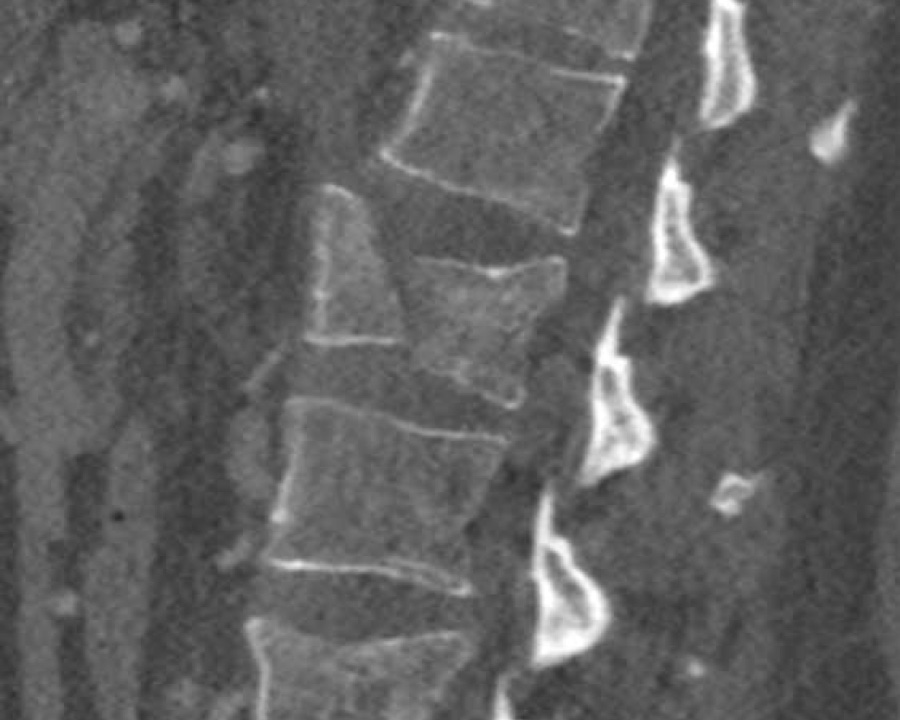

Findings:

- No C or B injury

- Fractures vertebral body with involvement of upper endplate (1 point) and posterior wall (2 points)

Conclusion

Injury type A3